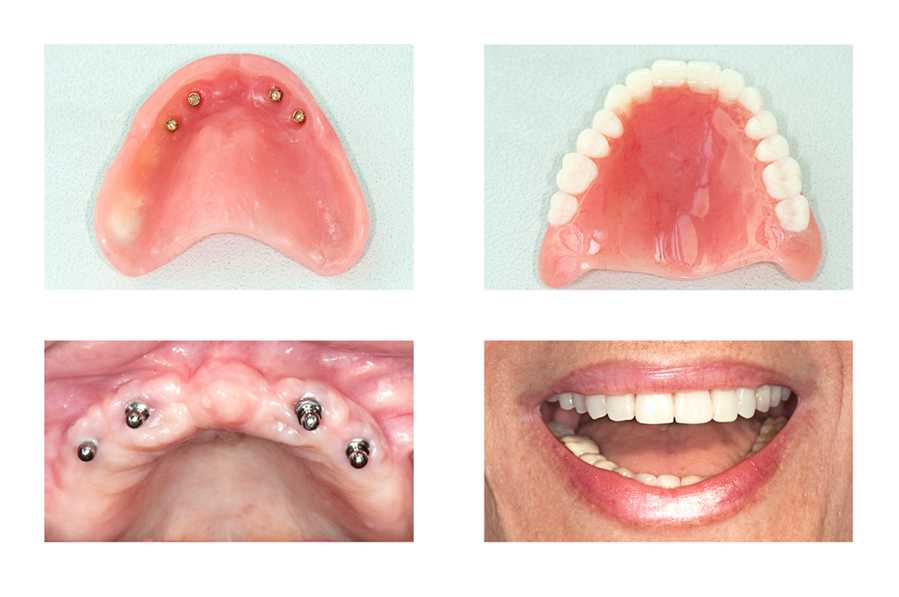

Advances In Dental Implantology